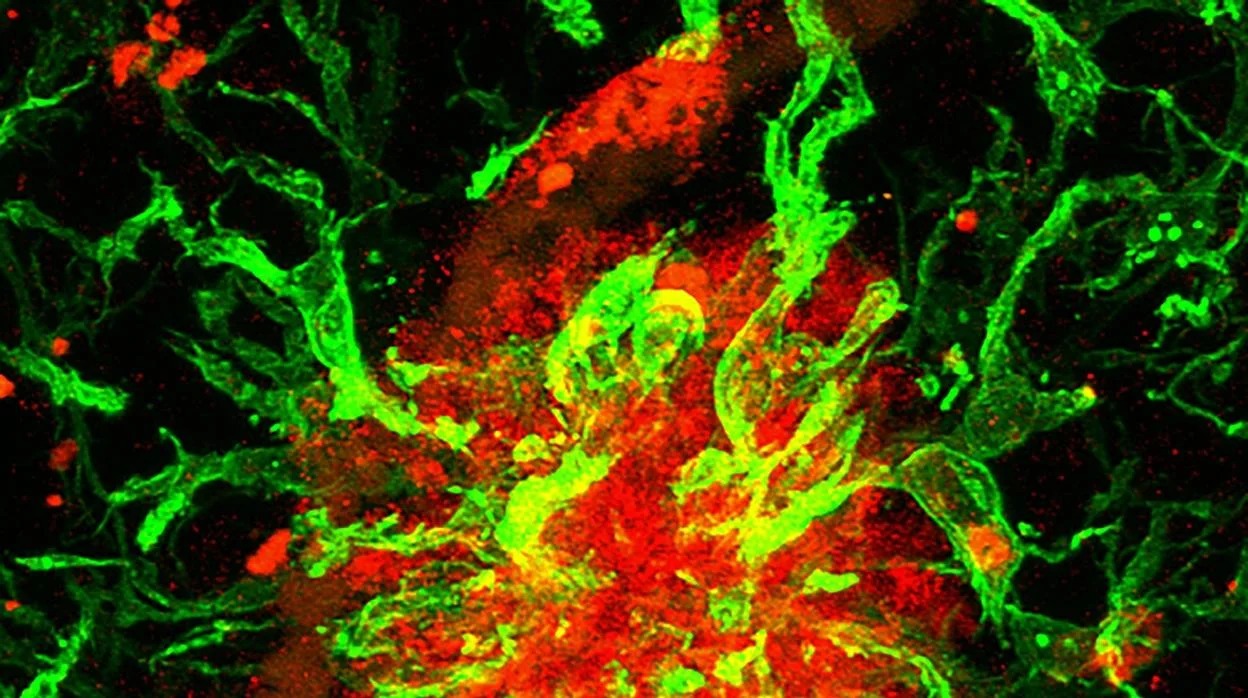

Descubren Proteína SFRP1 que Podría Desencadenar el Alzhéimer Años Antes de los Síntomas

Investigadores de España y Países Bajos hallaron que la acumulación de SFRP1 bloquea mecanismos clave para la memoria y plasticidad neuronal

Recientemente, investigadores de España y Países Bajos identificaron un mecanismo vinculado al desarrollo temprano del alzhéimer, mucho antes de la aparición de los síntomas más conocidos de la enfermedad, como la pérdida de memoria y la acumulación de placas beta-amiloide. El componente central de dicho mecanismo es una proteína llamada SFRP1, producida en exceso por células gliales del cerebro.

Los astrocitos y la SFRP1

Durante años se pensó que la células gliales (específicamente los astrocitos) no eran responsables de nutrir a las neuronas. Sin embargo, este nuevo estudio muestra que su rol en el origen del alzhéimer de estas células es mucho más activo. En condiciones normales, los astrocitos producen SFRP1 para regular la comunicación celular durante el desarrollo cerebral. No obstante, en cerebros adultos, esta proteína puede acumularse y volverse perjudicial.

Según un comunicado de prensa, los investigadores crearon un modelo basado en ratones. Dicho modelo mostró que un exceso de SFRP1 bloquea la función de una enzima llamada ADAM10, encargada de proteger y mantener las conexiones entre neuronas. “Este bloqueo genera un desequilibrio que deteriora la plasticidad sináptica, un mecanismo celular esencial para formar y consolidar recuerdos que permite a las neuronas regular su conectividad en respuesta a diferentes estímulos”, explicaron.